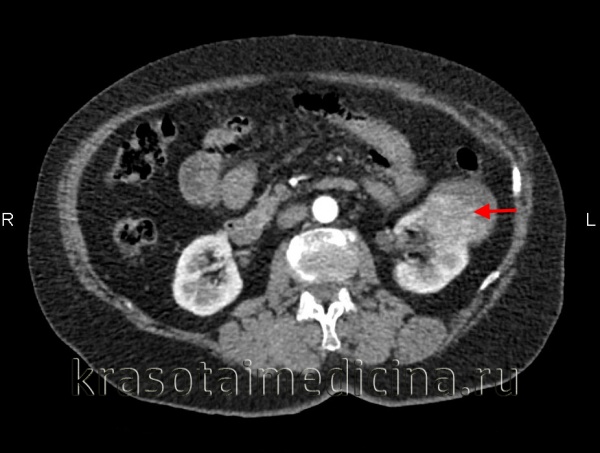

3. КТ при почечноклеточном раке:

• Обзорная КТ:

о Солидная опухоль или сложная киста, гипер-, изо- или гиподенсивное по сравнению с паренхимой почки

о Гетерогенное образование (кровоизлияние и некроз)

о Кальцификаты имеют высокую положительную прогностическую значимость в диагностике злокачественных новообразований, как в аморфных, так и в твердых структурах

о Внутриопухолевая жировая клетчатка встречается крайне редко и сопровождается костной метаплазией

• КТ с контрастированием:

о Степень контрастного усиления играет ключевое значение в дифференцировании различных подтипов ПКР

о Светлоклеточный ПКР: гиперваскулярный, гетерогенный, смешанный тип контрастирования: контрастирование мягких тканей сочетается с очагами некроза

- Контрастирование выше, чем при других подтипах

о Папиллярный ПКР: гиповаскулярный, обычно однородный; может быть частично кистозным

о Варианты кистозного ПКР:

- Одно- или многокамерное кистозное образование с утолщенной стенкой и узелковыми образованиями, контрастирование ровных или узловатых перегородок

о Встречается диффузный инфильтративный ПКР или с инфильтрированием чашечно-лоханочной системы

о Рентгенонегативный контур (псевдокапсула)

о Прямое инфильтрирование почечной вены (ПВ) (20-35%), нижней полой вены (НПВ) (4-10%), прилежащих мышц и внутренних органов